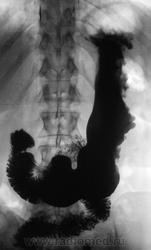

Лежа бы вниз головой... Ну а так, дефект наполнения по большой кривизне свода. М.б. что угодно, больше за гиперплазию или онко.

Тугое заполнение свода + можно пасс. рефлюкс, или не там патологию вижу? Просто стол опустить с пациентом ( который стоя стоит) на 10-15градусов без вычурных.

Почему не локальная форма Менетрие?....

"Картинка" то типичная, именно, для болезни Менетрие.

Менетрие? По одному снимку, без второй порции бария, без шипучки и снимков в горизонтальном положении. Как-то лихо.